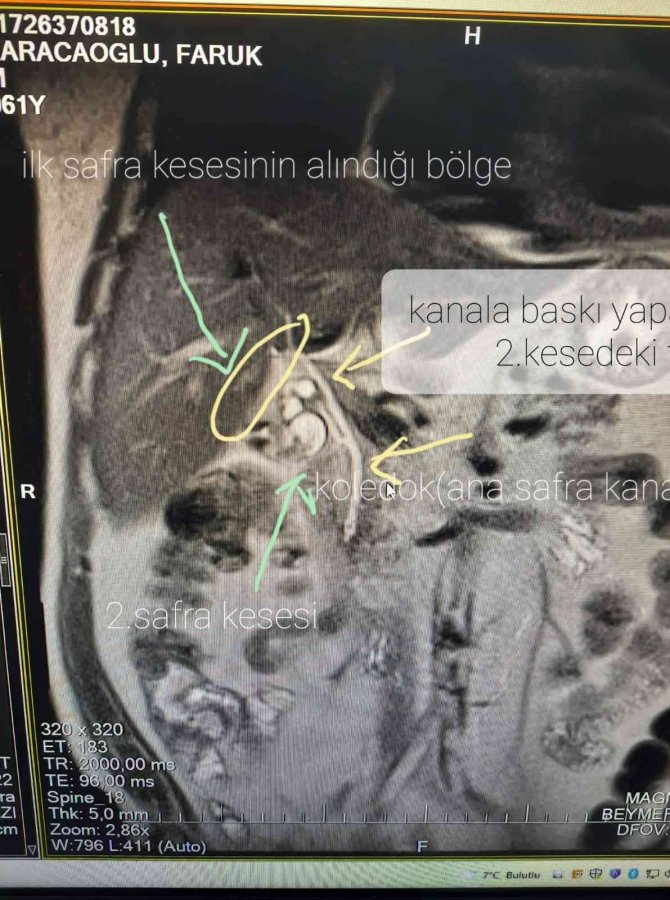

Safra kesesinin normal olanının ilk alındığını belirten Dr. Koçberber, "Safra kesesinin hem kanalı hem de damarının çift olması nadir bir durum. Yıllar önce benim bir hastamın da başına gelmişti. Bu hastamız 12-13 sene önce başarılı bir şekilde safra kesesi ameliyatı geçirmiş. Safra kesesinin orijinal yerinde olanı alınmış. Ancak normal yerinde olmayan arka tarafta yeni bir kanalı olarak ayrı damarı olan daha farklı ikinci safra kesesi varmış. Yıllar içerisinde bu kesenin içerisinde taşlarda oluşmuş. Hastamız farklı semptomlarla doktorlara gitmiş ama safra kesesi alındığı için ilaç tedavisiyle geçiştirilmiş" dedi.

İlerleyen süreçte ikinci safra kesesinin önemli etkenlere neden olabileceğini ifade eden Dr. Koçberber, "Hastamızı dün kapalı bir şekilde ameliyat ettik ve bu ikinci safra kesesini biraz zorda olsa aldık. Bizde doktorlar olarak safra kesesinde ameliyat oldu diye ayrı bir safra kesesi olduğunu düşünüp buna göre hastada ileri tetikleri yapmamız gerekiyor. Ana safra kanalı dediğimiz poledok kanalına baskı yapıp neredeyse çürümesine, tıkanıklığına sebep olup hayati tehlikede oluşturabilirdi" diye konuştu.